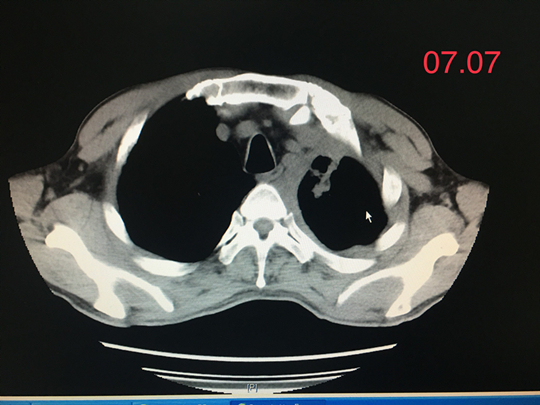

正当我们为王先生担忧的时候,基因检测结果回来了,EGFR基因存在17号和19号两个外显子突变,这无疑为王先生的下一步治疗明确了方向——靶向治疗!于是王先生开始口服吉非替尼片,服药过程中曾出现轻度的口腔黏膜反应,其它无明显的异常表现。

就这样过了两个月,王先生再次复查胸部CT,发现其左肺肿瘤病灶基本消失了,治疗效果非常好!